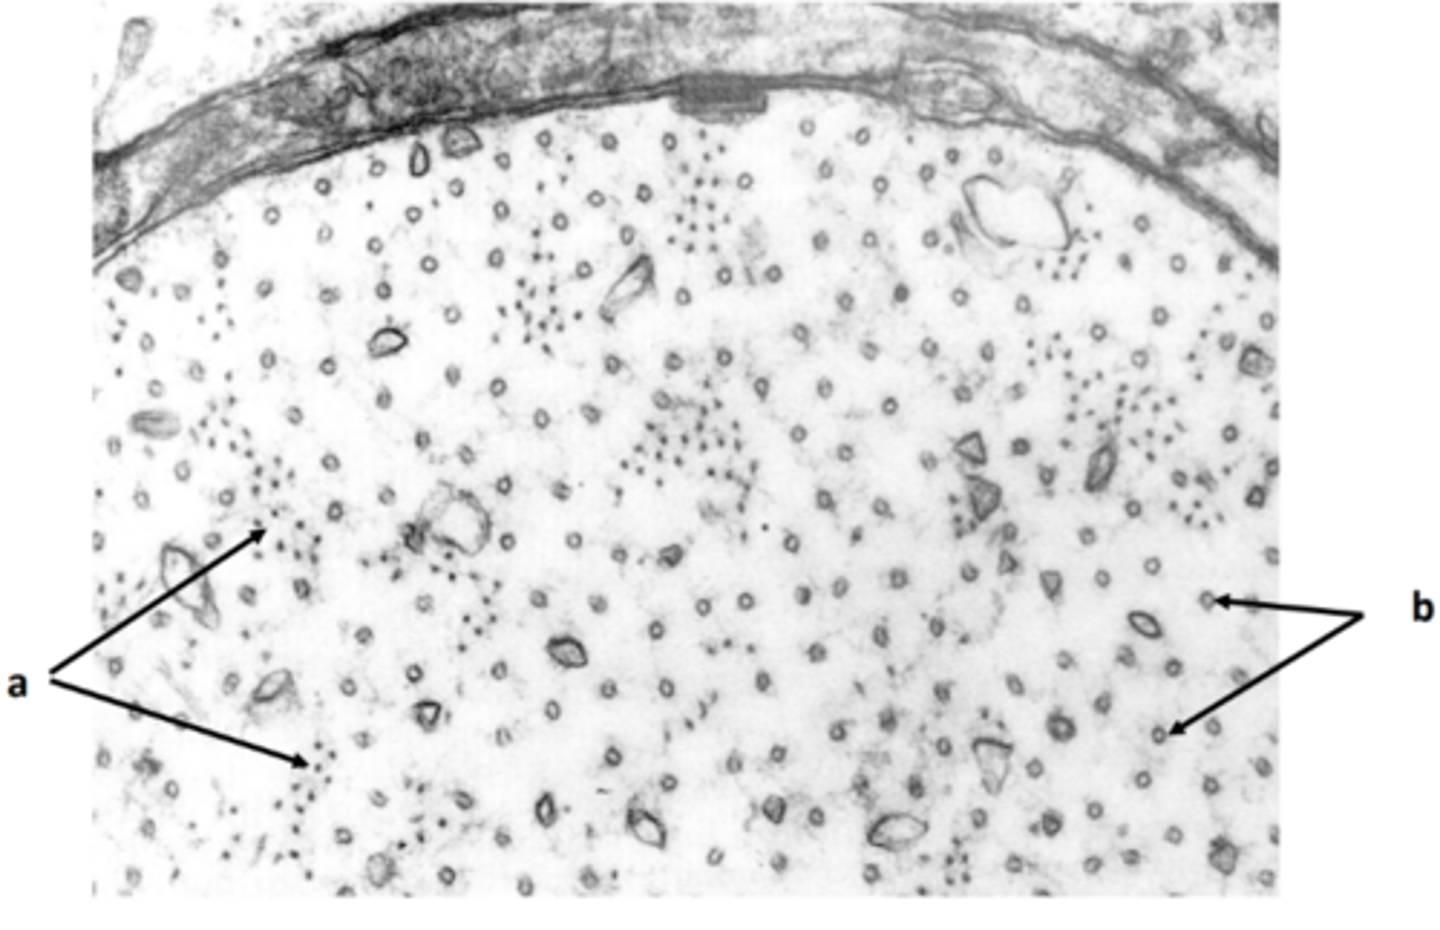

New cards

axon

a: structure

<p>a: structure</p>

neurofilament

22

neurotubule

b: structure

<p>b: structure</p>

23

Schwann cell cytoplasm

red: structures

<p>red: structures</p>